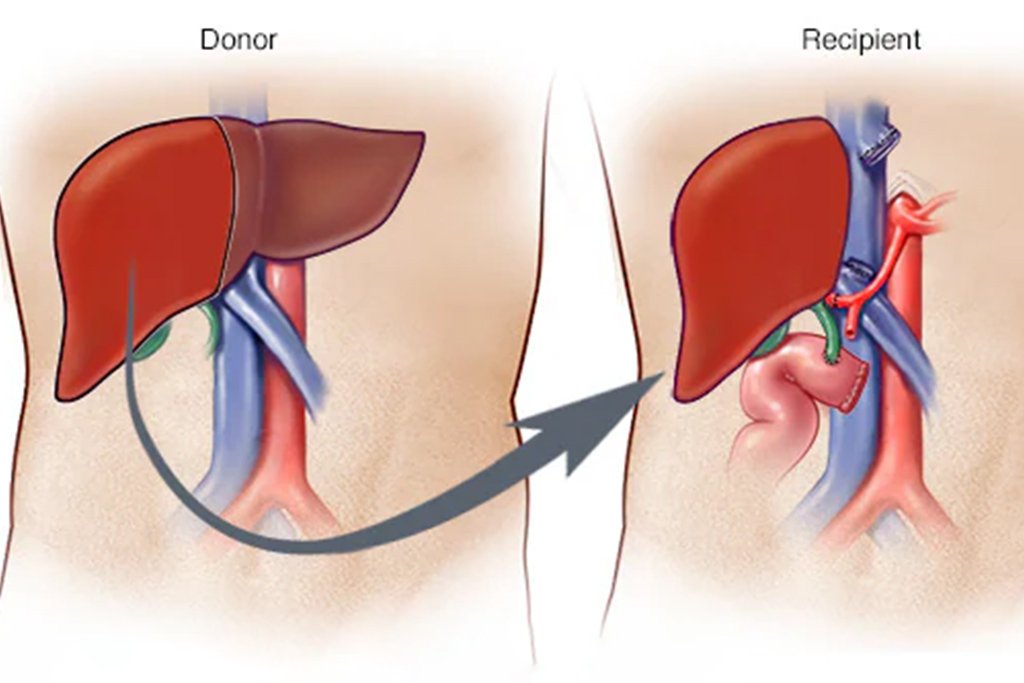

Liver transplantation is a complex surgical procedure in which a damaged or non-functioning liver is replaced with a healthy one from a donor. It is often the only viable treatment for patients facing end–stage liver disease, acute liver failure, or certain liver cancers.

Living Donor Liver Transplant (LDLT)

- Involves transplanting a portion of the liver from a healthy living donor (usually a close family member).

- The donor’s liver regenerates over time, restoring full function.

- Minimally invasive techniques like laparoscopic and robotic donor hepatectomy ensure faster recovery for the donor

During Surgery

- The transplant is performed under general anesthesia

- The damaged liver is removed and replaced with the healthy donor liver

- The blood vessels and bile ducts are reconnected to ensure normal liver function